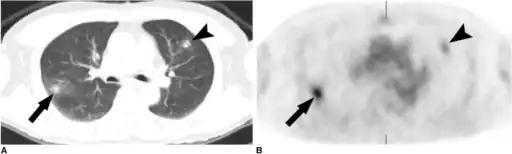

a,b)Simple pulmonary eosinophilia in an individual on both the CT and PET

The diagnosis of Loffler's syndrome can be challenging, as the diagnostic criteria can be vague and consistent with a multitude of diseases or conditions. The disease's developmental trajectory is mostly unknown. Upon examination of symptoms, a doctor will likely request a chest x-ray looking for migratory pulmonary infiltrate, and blood testing, to confirm a diagnosis. Symptoms tend to be brief, but can range from mild to severe and include: fever, vomiting, increased respirations or difficulty breathing, cough, wheeze, and rash. Symptoms typically follow an exposure to allergens or certain drugs, and last approximately two weeks.[4]